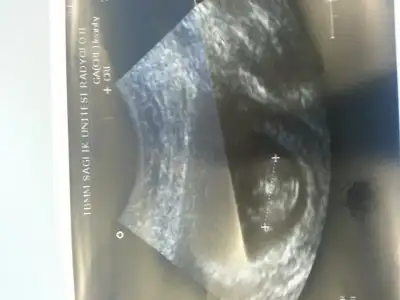

Merhaba arkadaşlar benimde ultrason resmimi yorumlarmısınız? Şimdiden çok teşekkürler:)